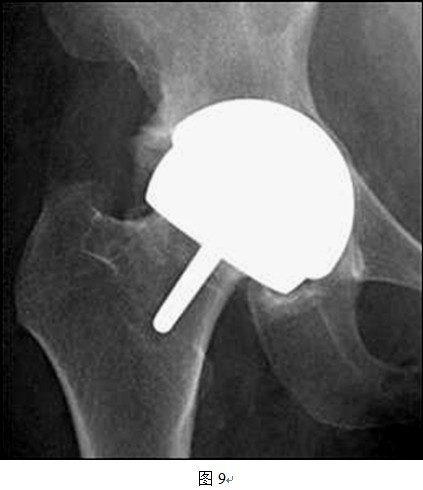

(1)头和臼假体之间有时很难良好匹配

DDH患者的髋臼发育不规律,头臼的匹配程度远远差于正常髋关节,而THRA的头臼假体间是一对一大小匹配,所以对于发育偏小的髋臼,按照髋臼侧决定THRA假体套件大小会出现股骨头过度磨锉,造成切迹;而按照股骨侧决定假体套件大小则会造成髋臼过度磨锉,大量骨质丢失,影响稳定性(图7、8所示即为以股骨侧决定假体大小时,髋臼侧出现过度磨锉,以致锉穿髋臼底部)。同样道理,对于发育偏大的髋臼,按照髋臼侧选择假体大小会造成人为的股骨颈缩窄(图9中所示病例以髋臼侧决定假体大小,导致股骨侧假体过大,反衬出股骨颈细小),而按照股骨侧决定假体型号则可能会出现髋臼软骨磨锉不充分,也可能影响髋臼假体稳定性(图10中所示病例以股骨侧选择假体大小,原始髋臼对于臼杯假体相对偏大,臼杯边缘的软骨尚未充分磨锉)。

图中所示,按照髋臼侧决定假体大小原则,匹配的股骨侧假体较股骨头颈来说偏大,造成人为股骨颈缩窄现象。

图中所示,按照股骨侧决定假体大小原则,匹配的髋臼假体较原始臼来说过小,髋臼磨挫不充分,假体与髋臼匹配不良。